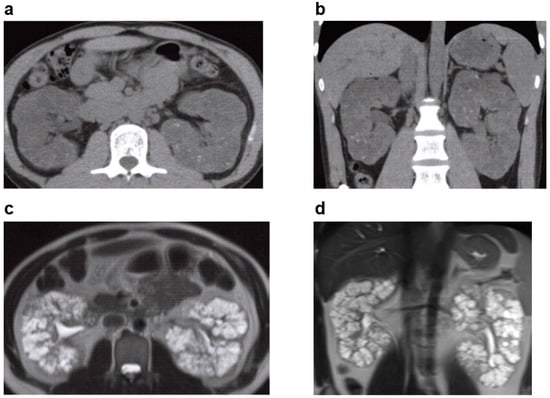

3.6.1. Tuberous Sclerosis (TSC)

| TSC | TSC1, TSC2 | AD | 1/10,000 | Hamartoma in the skin, nervous system, kidney, lung, bone, and elsewhere. Renal lesions; angiomyolipoma (AML), renal cysts, renal cell carcinoma. |